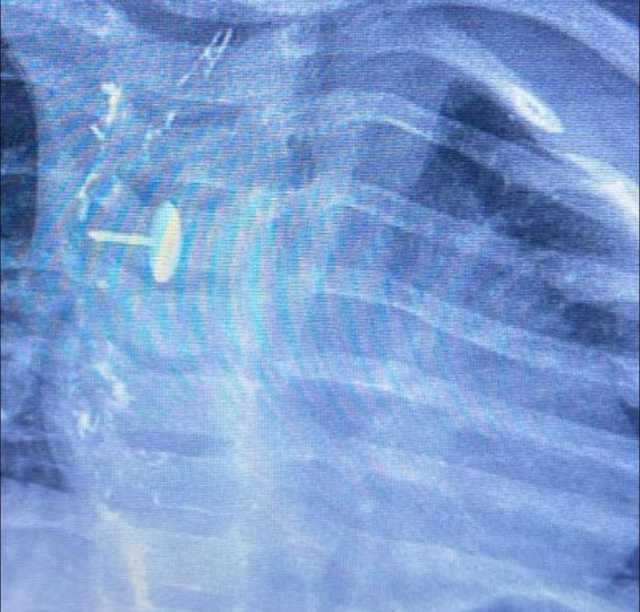

نجح فريق قسم جراحة الأطفال، بمستشفى الأطفال التخصصي ببنها، بمحافظة القليوبية، بقيادة الدكتور محمد متولي رئيس قسم جراحة الأطفال، في إجراء عملية دقيقة لاستخراج دبوس ضغط من مريء طفلة عمرها سنة و7 أشهر، كانت قد ابتلعته منذ 6 أشهر.

كشفت مستشفى الأطفال التخصصي ببنها، في بيان لها، أن الجسم الغريب استقر داخل جدار المريء، مما تسبب في عدم قدرة الطفلة على البلع طوال هذه الفترة، وجعل حياتها في خطر دائم.

أوضحت المستشفى أن العملية تمت باستخدام منظار الجهاز الهضمي، وجهاز الأشعة "سي- آرم"، ومنظار القصبة الهوائية، وسط أعلى درجات التركيز والدقة، ليكتب الأطباء نهاية سعيدة لقصة مليئة بالتوتر والخطر